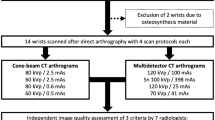

A twin robotic x-ray system with new CBCT mode and a high-resolution clinical MDCT were compared in 16 cadaveric elbows. Both systems were operated with a dedicated low-dose (LD) protocol (equivalent volume CT dose index [CTDIvol(16 cm)] = 3.3 mGy) and a regular clinical scan dose (RD) protocol (CTDIvol(16 cm) = 13.8 mGy). Image quality was evaluated by two radiologists (R1 and R2) on a seven-point Likert scale, and estimation of signal intensity in cancellous bone was conducted. Wilcoxon signed-rank tests and intraclass correlation coefficient (ICC) statistics were used.

For this study, however, we decided to use constant tube currents to provide comparable circumstances for both imaging modalities. To compare the applied radiation dose between CBCT and MDCT, the dose-area product of the CBCT scan mode was multiplied by a linear scaling factor leading to volume computed tomography dose index (CTDIvol)-equivalent values. By using a polymethyl methacrylate dosimetry phantom, conforming to International Electrotechnical Commission 60601-2-44:2009 with a total length of 300 mm and a diameter of 160 mm as well as a standard dosimetry system (Nomex Dosimeter, PTW, Freiburg, Germany) with a 300 mm ionisation chamber, the scaling factor for each combination of voltage, pre-filtration and acquisition geometry was calculated in advance. To achieve this, the dose-length product (DLP) was quantified in five chambers. Then, the standard weighting scheme for dose measurements was applied to each value to determine the DLPvol values. CTDIvol values were calculated by dividing the DLPvol by the beam width (equivalent to the field of view in the z-direction), and to finally compute the scaling factor, CTDIvol was divided by dose-area product values. We operated with a dedicated low-dose (LD), i.e., CTDIvol(16 cm) = 3.3 mGy, and a regular dose protocol (RD) comparable to our clinical scan protocol, i.e., CTDIvol(16 cm) = 13.8 mGy), for both systems. MDCT images were acquired using the CT scanner in single-energy mode. Scan parameters for CBCT and MDCT studies are displayed in Table 1.